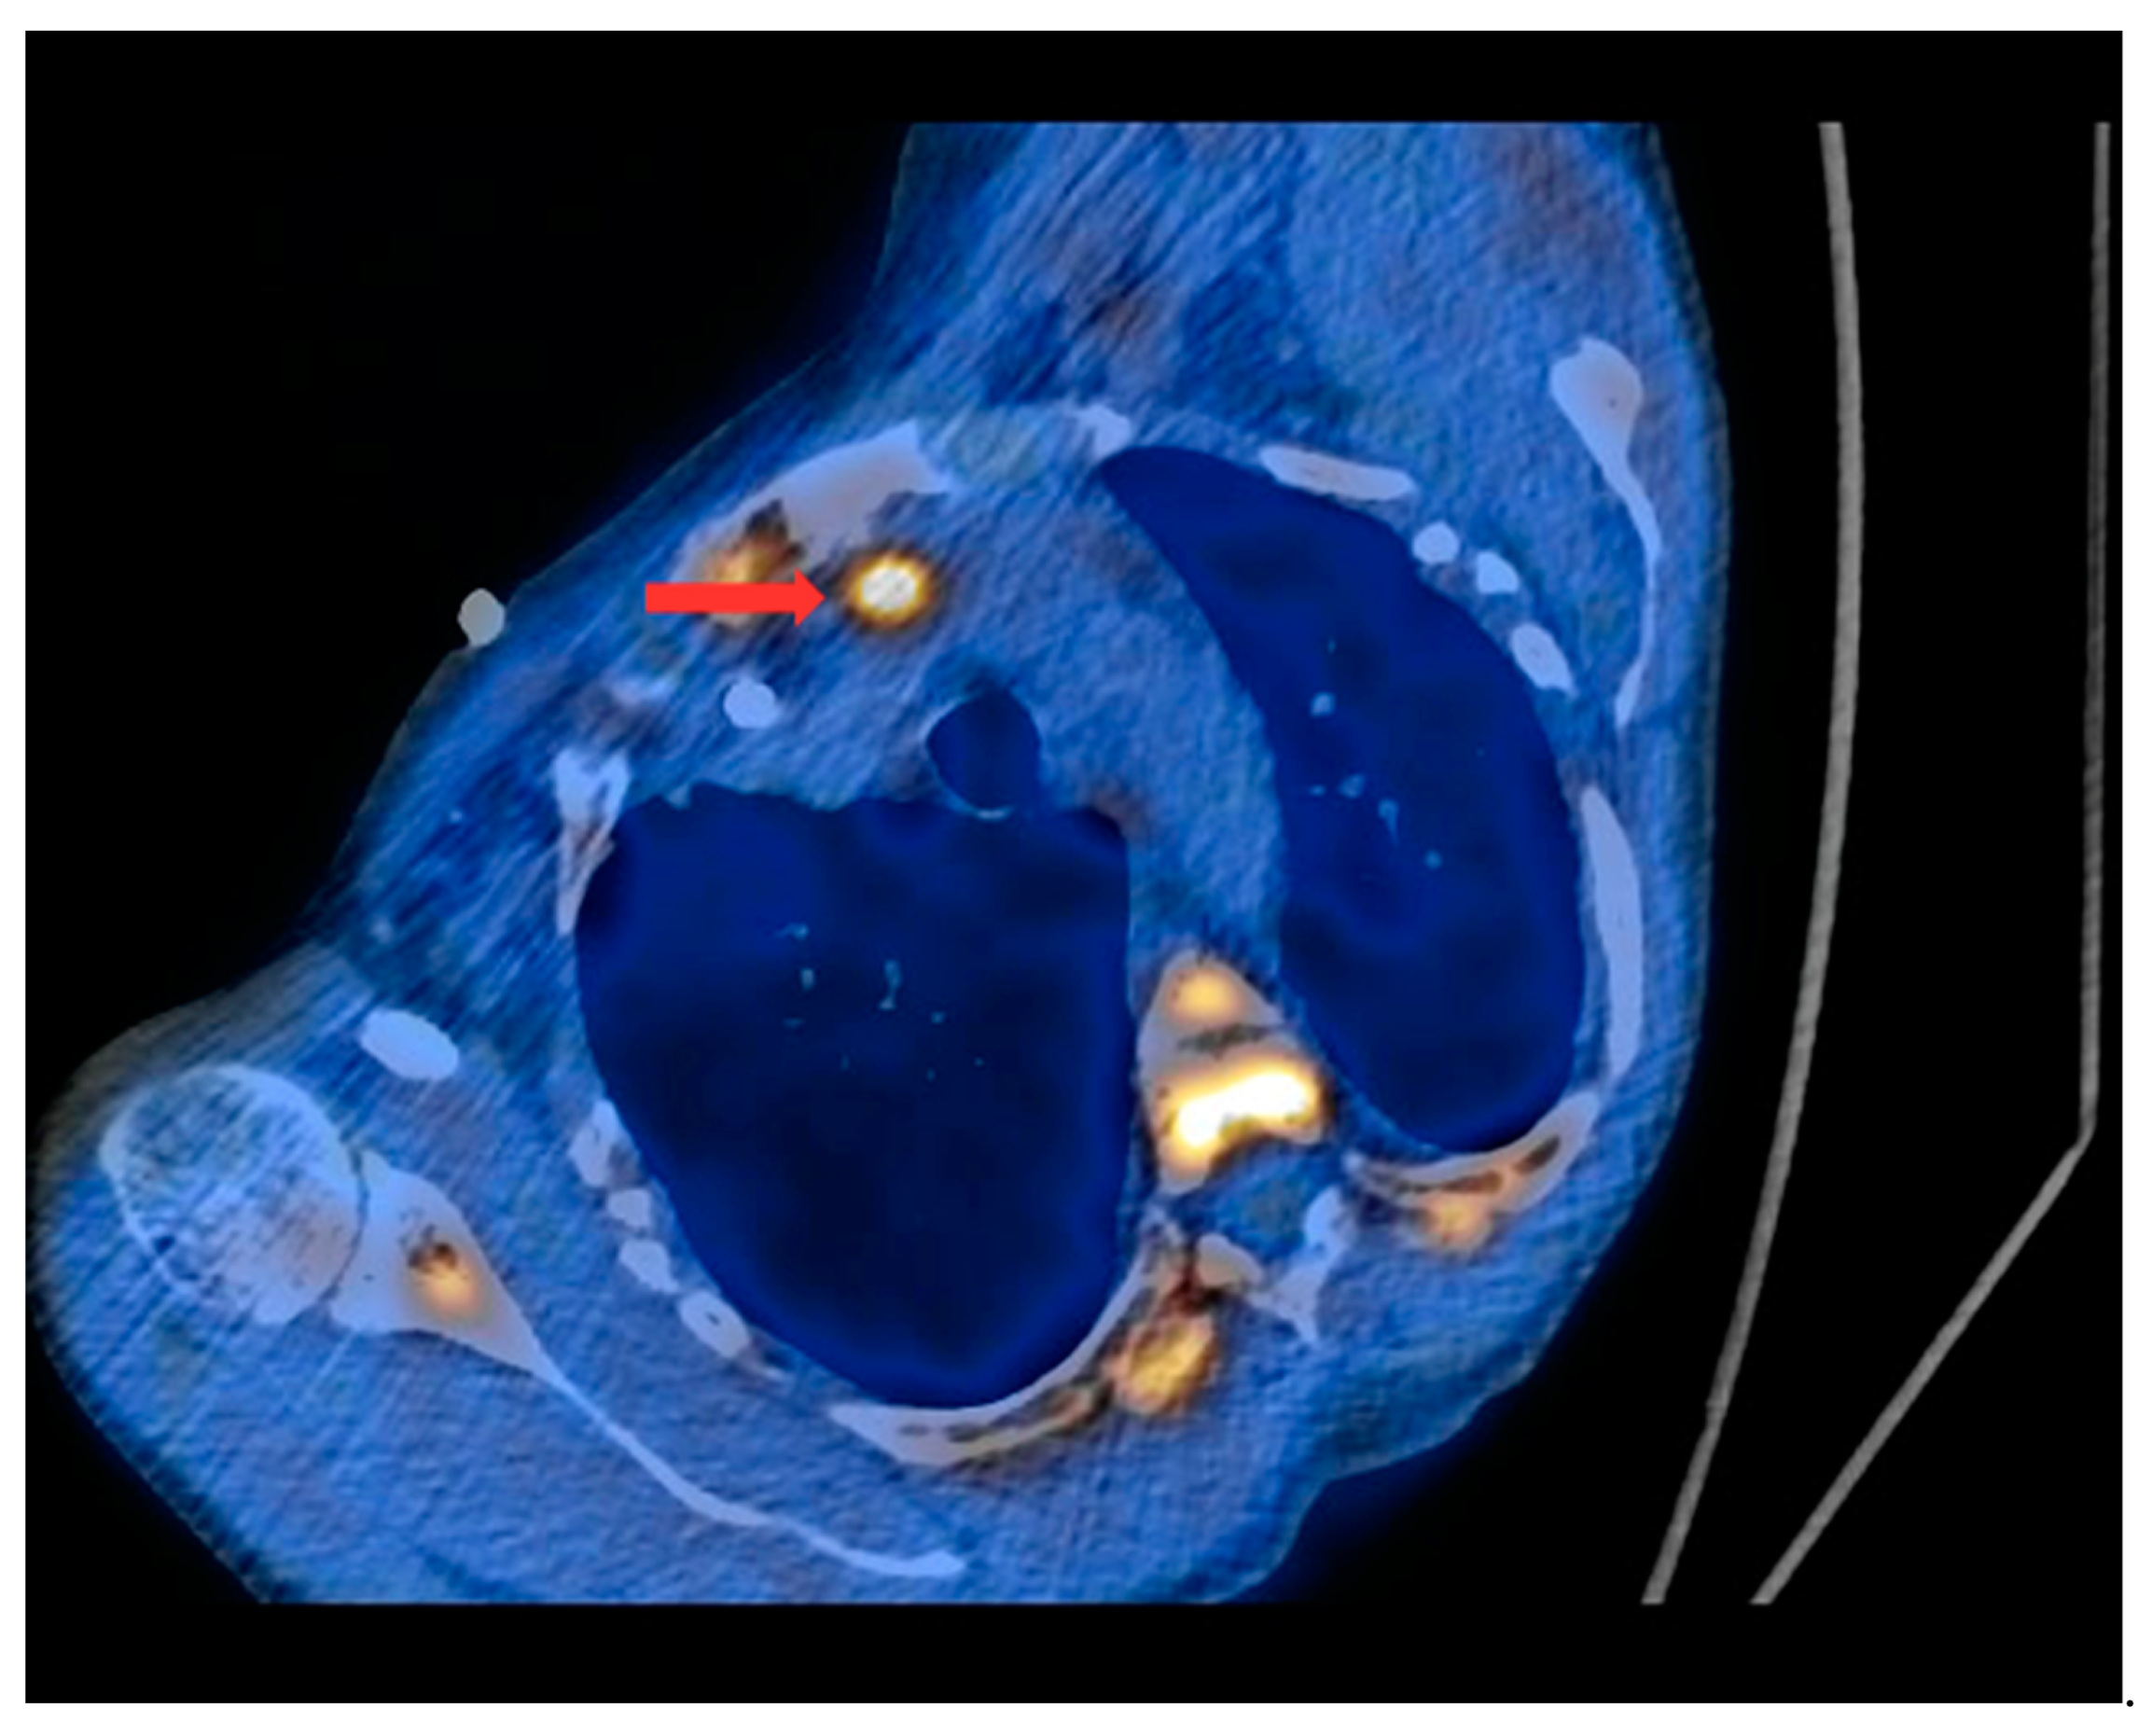

PET/CT with [11C]MET was performed on 19 patients, with negative results for both first-line imaging examinations. In this group, a positive result was obtained in 89.5% of the patients (17/19) (Figure 1 and Figure 2). In 2 patients (10.5%), the result was assessed as inconclusive (both of these patients showed accumulation of the radiotracer in a single lesion, the location and structure of which indicated that it might be a mediastinal lymph node; however, these lesions were not histologically verified due to revealed contraindications for surgery). Multiple lesions were observed in 57.9% of the patients (11/19) (Figure 3). Ectopic lesions were observed in 21.1% of the patients (4/19) (Figure 4). In total, 34 foci of increased accumulation of the radiotracer, considered as parathyroid glands, were observed. Additionally, in 15.8% of the patients (3/19), foci of increased accumulation of the radiotracer in the bones corresponding to brown tumors were observed (Figure 5a,b). Detailed results of the PET/CT examinations with [11C]MET are shown in Table 1.

Figure 4.

PET/CT with [11C]MET—axial projection. During the examination, the patient was laid at her left side due to the forced body position caused by numerous fractures and a brown tumor infiltrating the spinal canal (as a result of tHPT). Visible focus of increased radiotracer uptake (red arrow) in the lesion corresponding to the ectopic parathyroid gland, located in the left superior mediastinum retrosternally, and anteriorly from the initial segment of the aortic arch.